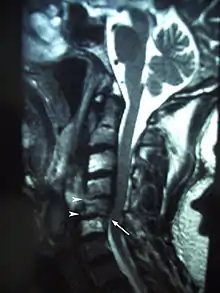

Osteoradionecrosis (ORN) is a serious complication of radiation therapy in cancer treatment where radiated bone becomes necrotic and exposed.[1] ORN occurs most commonly in the mouth during the treatment of head and neck cancer, and can arise over 5 years after radiation.[2] Common signs and symptoms include pain, difficulty chewing, trismus, mouth-to-skin fistulas and non-healing ulcers.

There are not many specific clinical signs of ORN.[10] It may be first seen as an area of exposed bone which is not healing, or the non-specific signs may become evident prior to this. Symptoms vary depending on the degree of ORN that has occurred. Early indicators may be numbness or paresthesias within the mouth or jaw. Other signs and symptoms include: